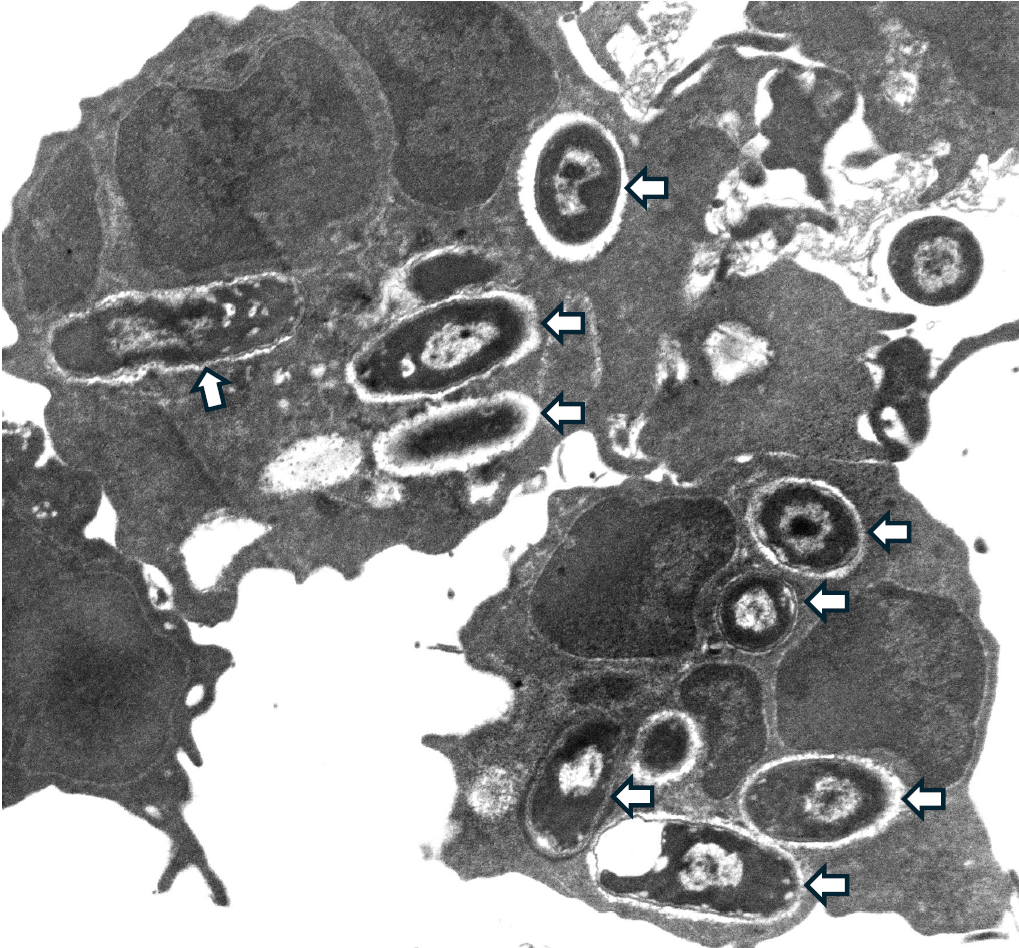

Acute pyelonephritis is a serious kidney infection that develops when bacteria spread from the bladder to the kidneys. This typically happens when bacteria such as UPEC travel upwards through the ureters, the tubes connecting the bladder and kidneys. These microbes are well adapted for the journey: they use hair-like structures called fimbriae to attach to the urinary tract lining, tail-like flagella to move forwards and can even enter the cells lining the tract to avoid being flushed out with urine or detected by the immune system. In children with a condition called vesicoureteral reflux — where urine flows backwards towards the kidneys — this spread is more likely.

Neutrophils are the most common type of white blood cell and are among the first immune cells to arrive at a site of infection. Although they live for less than a day, they respond quickly, engulf invading bacteria and destroy them. Juan’s research highlights how important they are in UTIs caused by UPEC. In mouse studies, when neutrophils are absent, bacteria spread rapidly, leading to more severe kidney infections and greater tissue damage, mirroring observations in human patients with low neutrophil counts.

Inside neutrophils, an enzyme called NADPH oxidase plays a crucial role in the elimination of UPEC. After a bacterium is engulfed, NADPH oxidase produces reactive oxygen species — toxic molecules that help kill the microbes. But NADPH oxidase does more than destroy bacteria: it also helps control inflammation, preventing the immune response from becoming too strong and harming healthy kidney tissue. “We are currently investigating strategies to selectively enhance NADPH oxidase activation in neutrophils to boost their bacteria-killing ability, while avoiding harmful overactivation of the immune system,” says Juan. “Our preliminary results are promising; in mouse models, we see that activation of NADPH oxidase in neutrophils promotes bacterial killing, and we observe fewer bacteria in the kidneys.”